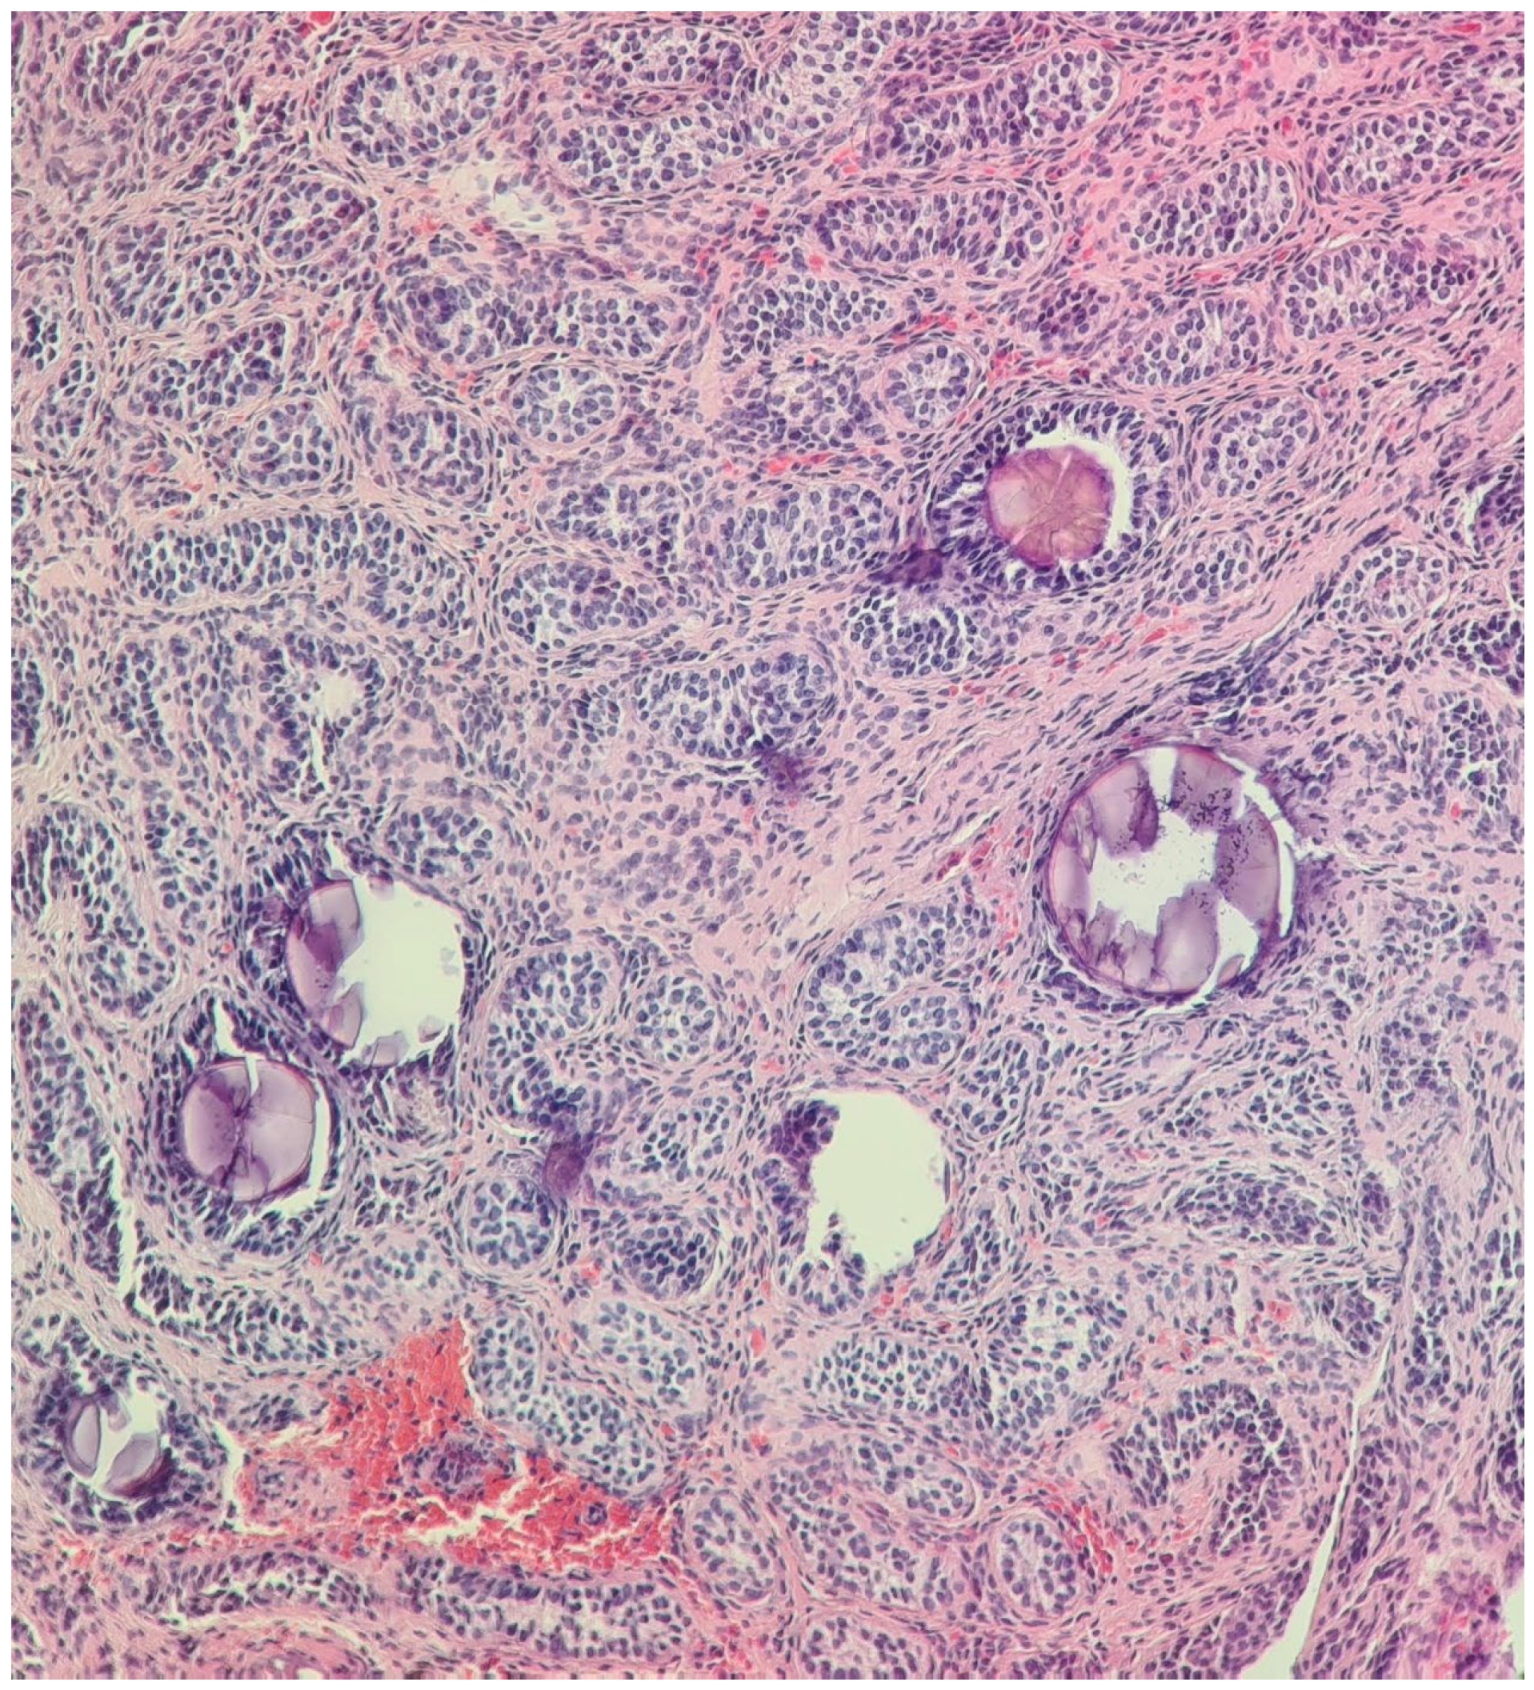

2.4. At Age 13 Years